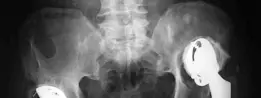

- الأشعة السينية الأمامية الخلفية للحوض (AP Pelvis X-ray): تُظهر هذه الصورة الوضع العام لمفصل الورك، وموقع الغرسة الحُقية، ومدى هجرتها. في حالة المريض، أظهرت الأشعة السينية تخلخلًا في حلقة مولر (Muller ring) وهجرة علوية جانبية لمركز الورك تزيد عن 3 سم. كما أظهرت تدميرًا في الحافة العلوية للحُق، مع بقاء خط كوهلر سليمًا، مما يشير إلى عيب Paprosky IIIA.

- الأشعة السينية للطرفين السفليين بوضعية الوقوف: تُستخدم لتقييم طول الطرفين وتحديد أي تشوهات في المحور مثل تشوه الفالج (Valgus deformity) وقصر في عظم الفخذ، كما لوحظ في حالة المريض (قصر 2 سم في الفخذ الأيمن).